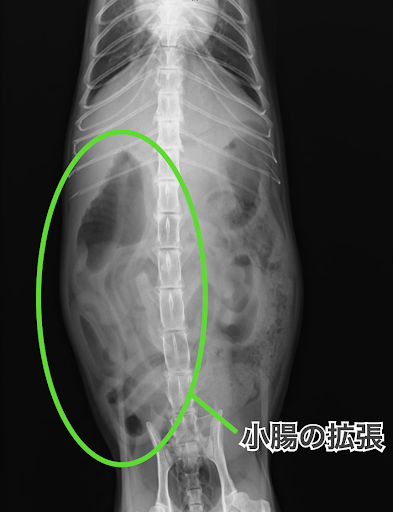

レントゲン検査では小腸の拡張とガスによる膨満が確認されました。

こちらがレントゲン画像です。